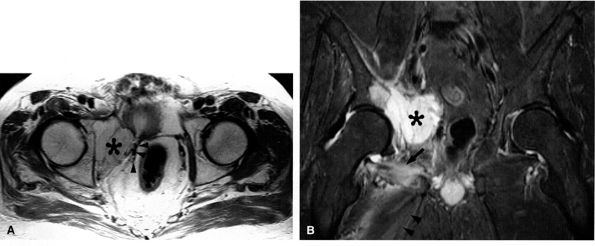

FIGURE 6.3 ● Proximal tibial entrapment in a 49-year-old patient with neuropathic foot pain. Symptoms resolved following an intra-articular steroid injection of the knee. This axial T2-weighted fat-suppressed image depicts a loose body in the popliteal muscle bursa (arrow), abutting on the neurovascular structures (arrowheads).There are many variations in muscle innervation and many communicating nerve loops in the lower extremity, particularly in the foot region.43 For example, the deep peroneal nerve may, in rare instances, supply muscles such as the adductor hallucis and flexor hallucis brevis, muscles typically innervated by the lateral and medial plantar nerves. This variability can affect the distribution of signal alterations within denervated muscles and may produce puzzling MR patterns. Familiarity with variations in innervation aids in interpreting unexpected muscle denervation signal alterations. -

Finally, the distance from the site of entrapment to the innervated muscle should be considered when searching for muscle denervation abnormalities. Proximal damage to the peroneal division of the sciatic nerve may depict denervation signal in the leg or foot. This signal alteration may be missed if only the thigh is being imaged. Similarly, MR imaging of a painful foot may overlook a more proximal entrapment in the leg or thigh (Fig. 6.3). It is important to pay careful attention to signal changes on sagittal and coronal planes, where larger portions of the limb are illustrated, to help avoid this pitfall. If the clinical suspicion for entrapment is high and no abnormalities are noted on the initial study, imaging a more distal or proximal section of the limb can also be performed.

FIGURE 6.25 ● Acetabular metastasis with obturator neuropathy and denervation edema. (A) An axial PD-weighted image depicts a hyperintense destructive acetabular mass (asterisk) medially displacing the obturator neurovascular structures (arrowheads). (B) This coronal T2-weighted fat-suppressed image of the pelvis demonstrates the acetabular mass (asterisk) medially displacing the pelvic structures. Subacute denervation edema in the obturator externus (arrow) and adductor muscles (arrowheads) is noted.